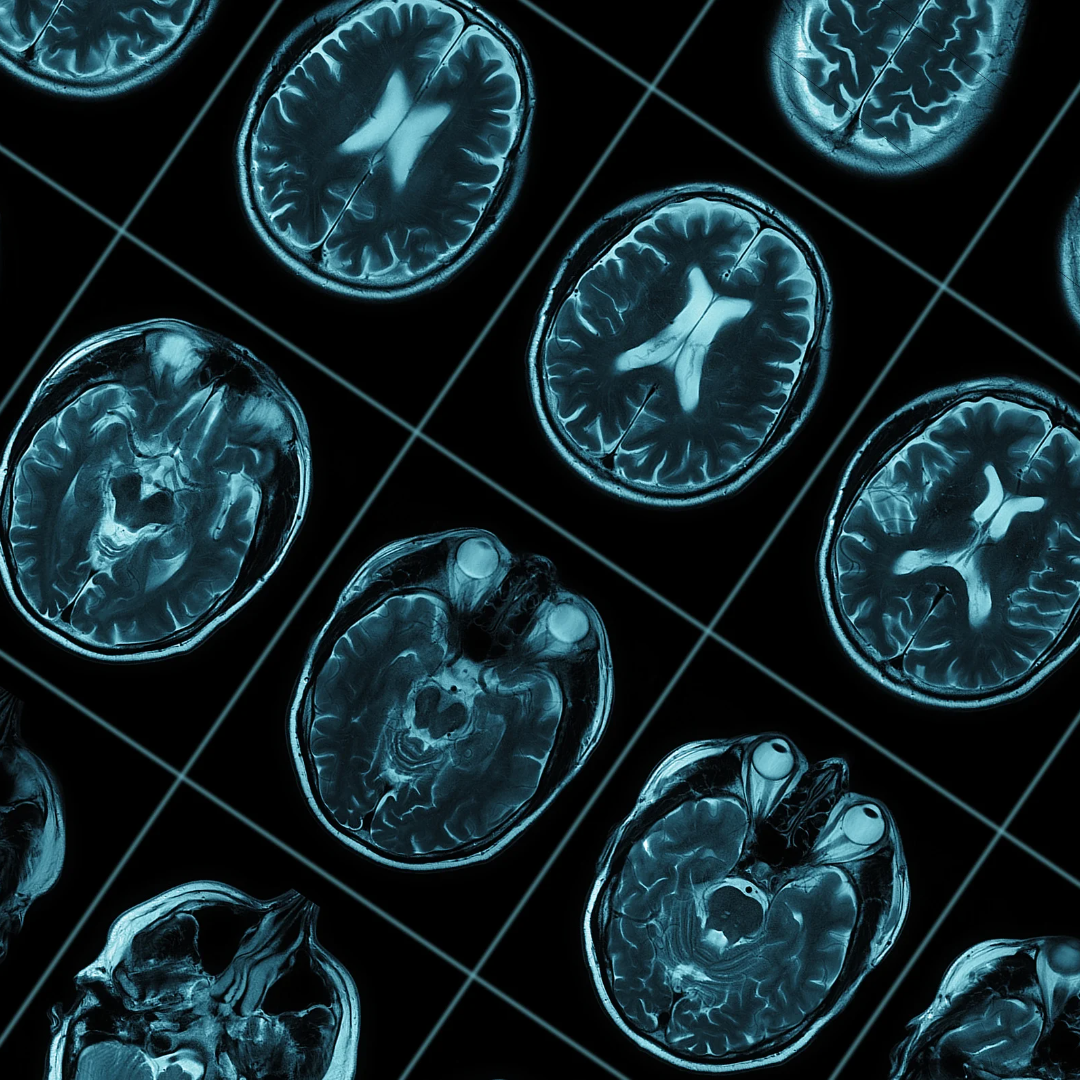

Managing the Cost of Alzheimer’s Care Through Early Disease Detection